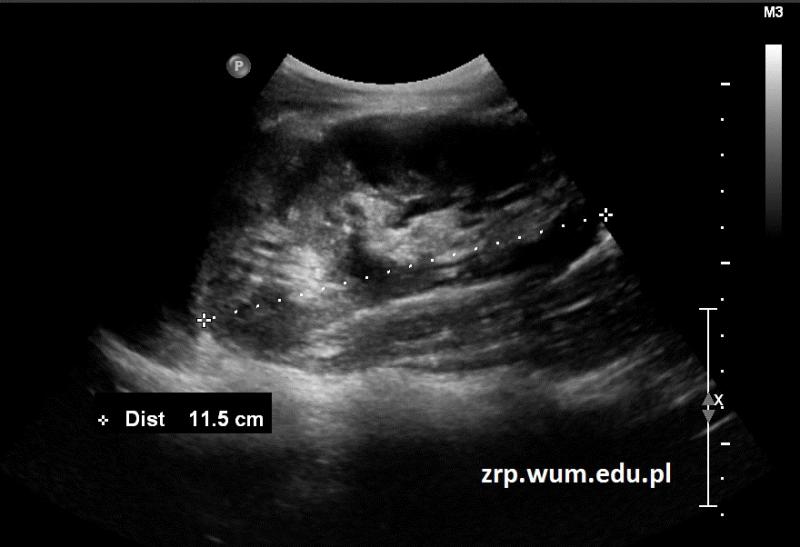

Przypadek 15: 16-latek ze stwierdzonymi w badaniu usg cechami zdwojenia układu kielichowo-miedniczkowego nerki lewej.

Rozpoznanie: W badaniu usg stwierdzono w nerce lewej dwa echa centralne (strzałki) z widocznym między nimi miąższem nerkowym. Bez poszerzenia UKM.